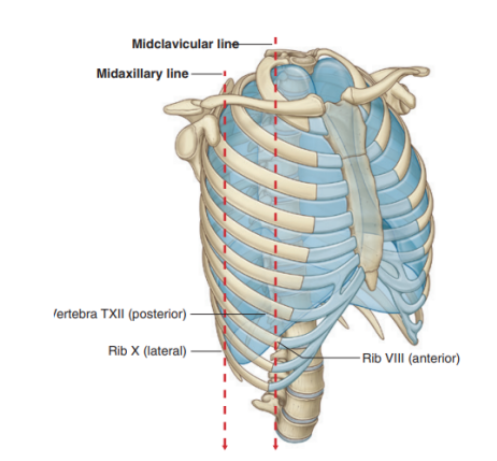

Also some vertical lines indicating extension of pleural cavity

Vertical lines indicating extension of the pleural cavity

Midclavicular line —

Pleural cavity extends inferiorly from the clavicles to approximately rib VIII

Midaxillary line —

Extends to rib X

Inferior margin of the parietal pleura takes an oblique path laterally from the level of rib VII in the midclavicular line to rib X in the midaxillary line and the T12 vertebra at the vertebral columns

Surface anatomy relating to the fissures and lobes

Palpable surface landmarks —

Can be used to visualize the normal outlines of the pleural cavities & lungs & to determine the positions of the pulmonary lobes & fissures —ex.

Superiorly, we can see the parietal pleura projects above the first costal cartilage & anteriorly approaches the midline posterior to the sternum (uppermost section). Left parietal pleura doesn’t come close to the midline as much as the right lobe due to the heart bulging on the left side

Inferiorly, the pleura reflects on the diaphragm, above the costal margin & courses around the thoracic wall following an VIII, X, XII contour

(Ie. rib VIII in the midclavicular line, rib X in the midaxillary line, and vertebra TXII posteriorly)

Margins of lungs related to ribs

Inferior lung margin —

Found at bottom of the thoracic wall, following a VI, VIII, X contour (ie. rib VI in the midclavicular line, rib VIII in the midaxillary line, and vertebra TX posteriorly)

Oblique fissure position —

Located in the midline, near the spine of vertebrae TIV, moves laterally downwards crossing fourth and fifth intercotal spaces and reaches VI laterally

Horizontal fissure(right side) —

Follows the contour of rib IV and its costal cartilage

Oblique fissures on both sides follow the contour of rib VI and its costal cartilage